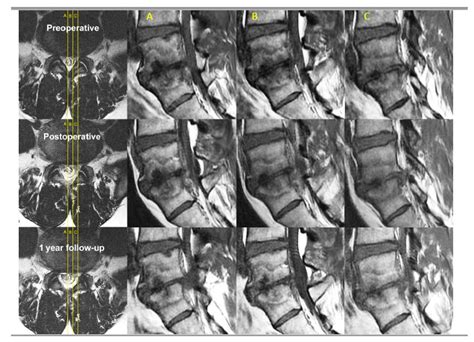

• Imaging Results: Confirmation of type 1 or type 2 Modic changes (vertebral endplate inflammation) on an MRI.

Clinical studies have consistently shown that Basivertebral Nerve Ablation provides durable relief for the majority of patients. Many individuals report substantial improvements in their Oswestry Disability Index (ODI) scores—a standard measure of how back pain impacts daily life—within just a few weeks of the intervention. Because the nerve does not typically regenerate in a way that restores the transmission of the original pain signals, the benefits can last for several years, allowing many patients to return to their favorite physical hobbies and occupations.